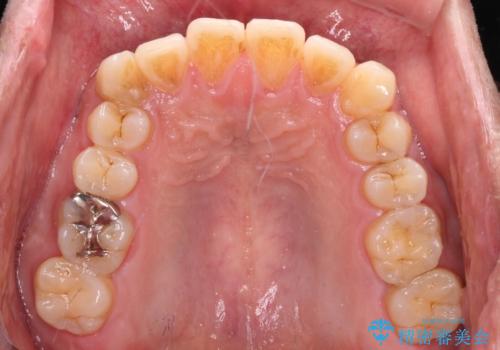

- 前歯のデコボコを気にして来院された患者様です。

当院でインビザライン矯正治療をされている方からのご紹介ということで、インビザラインでの矯正治療をご希望でした。

ワイヤー矯正に比べ来院頻度は低いものの、新幹線での通院のため、やや治療期間が延びることが懸念されました。